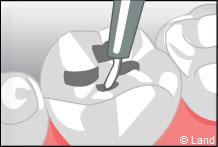

Les traitements possibles pour les stades de la carie où seuls l’émail et la dentine sont touchés peuvent se faire avec de l’amalgame qui est un matériau indiqué dans la restauration des petites et moyennes cavités.

L’amalgame est utilisé sous forme de capsules prédosées et avant son utilisation est préparé par un vibreur qui mélange les composants de façon homogène. Il se présente sous la forme d’une pâte, plastique qui durcit dans la cavité nettoyée de la lésion carieuse et devient pratiquement aussi résistant que les tissus dentaires.